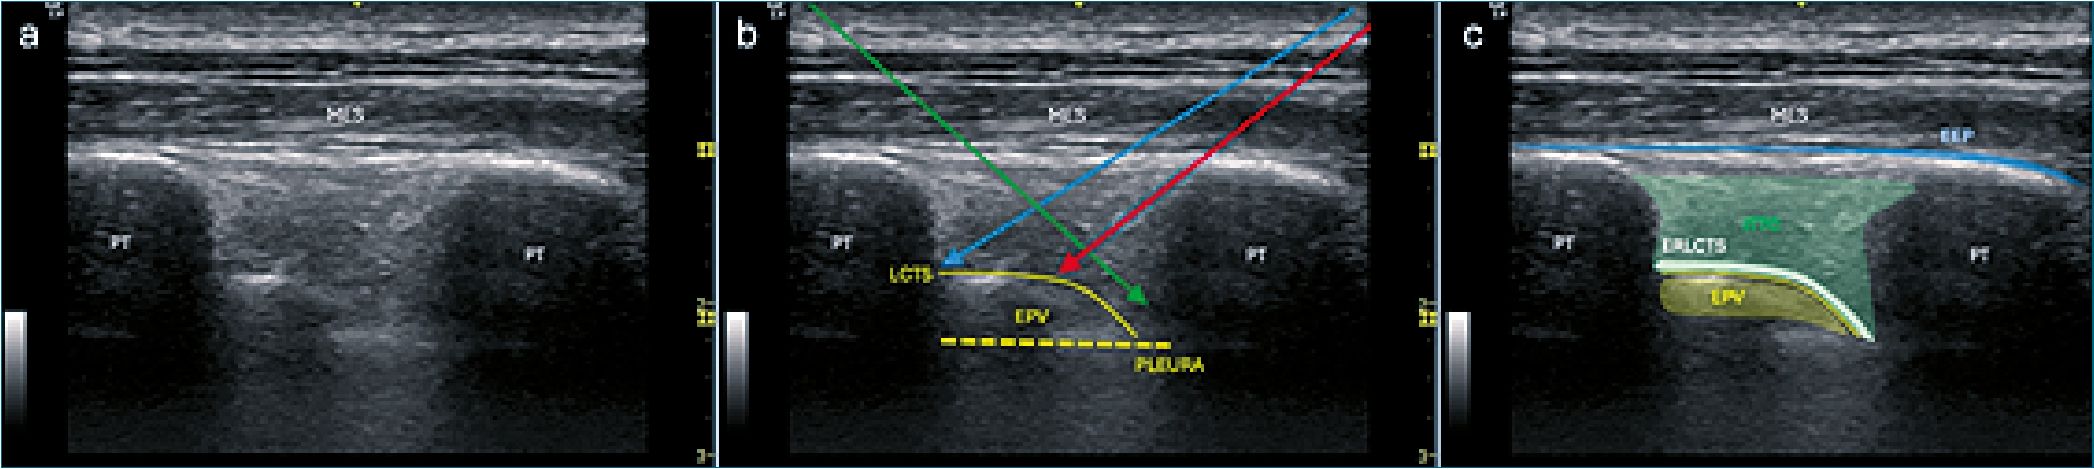

Basado en estos hallazgos, en 2017 Costache y colaboradores[7] proponen el “Mid-point transverse process to pleura block” (MTPB) como un nuevo y novedoso punto objetivo para bloqueos paravertebrales. Los autores realizaron esta descripción en cadáveres con una visión ultrasonográfica parasagital y con una aproximación en plano de caudal a cefálico en dirección hacia el EPV, pero ubicando la punta de la aguja a mitad de camino entre el plano de la apófisis transversa y la pleura. Se realizaron cinco punciones bilaterales en 3 cadáveres con 5 ml de azul de metileno donde se pudo observar con relativa frecuencia: visualización ultrasonográfica del LCTS, avance del inyectado hacia el espacio de los músculos erectores de la espina y desplazamiento pleural. En la disección de los cadáveres la tinción de la raíz nerviosa fue frecuente, no obstante, la de la cadena simpática fue variable. En el mismo estudio se describe la utilización de esta técnica en dos pacientes mujeres sometidas a cirugía oncológica de mama con biopsia de linfonodo centinela, donde se realizaron tres punciones (T2-T3-T4) con ropivacaína 0,5% o bupivacaina 0,25%, 10 ml cada nivel, posterior a la anestesia general, logrando buena respuesta clínica y mínimo uso de analgesia de rescate en el posoperatorio[7] (Figura 2).

Figura 2. a: Imágen sonográfica de espacio intertransverso; b: Abordajes paraespinales descritos; c: Áreas de interés anatómicas. MES: músculo erector de la espina; PT: proceso transverso; LCTS: ligamento costo transverso superior; EPV: espacio paravertebral; ERLCTS: espacio retroligamento costotransverso superior; EEP: plano erector de la espina; ITTC: intransverse tissue complex; Flecha roja: MPTPB (Costache 2017) o ITPB (actual); Fecha azul: STIL: block (Kilcasian 2020) o bloqueo del foramen costotransverso (Shibata 2020); Flecha verde: MICTB o CTB (Nielsen 2019).